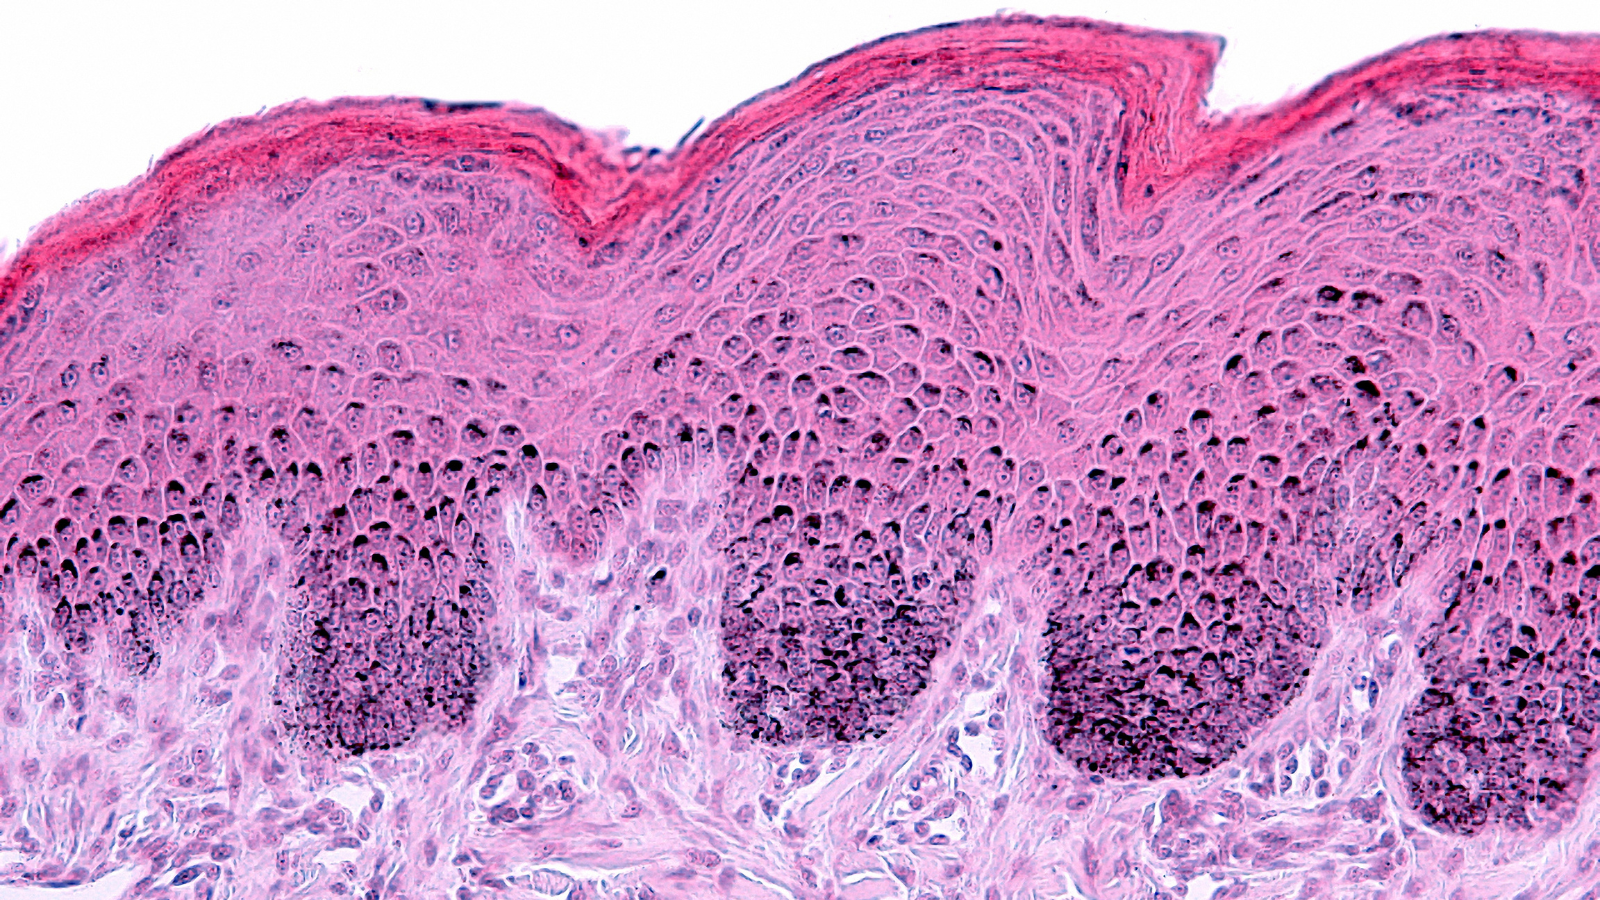

HDRS is a non-invasive test that combines both in vivo and in vitro processes to obtain a comprehensive understanding of efficacy. Through a non-erythemal (non-redness-inducing) optical assessment, it eliminates the need to induce erythema and pigmentation in subjects. In vitro measurements are fused with in vivo assessments to deliver instantaneous UVA-PF measurements, including a photostability assessment. In addition to being safer, HDRS offers faster turnaround times and is more cost effective.

Conventional in vivo sunscreen testing methods rely on exposing the skin to UV radiation to intentionally induce redness or pigmentation. While widely used and standardized, these methods raise ethical concerns. Meanwhile, fully validated in vitro alternatives that avoid human testing do not capture the essential factor of direct human skin exposure.